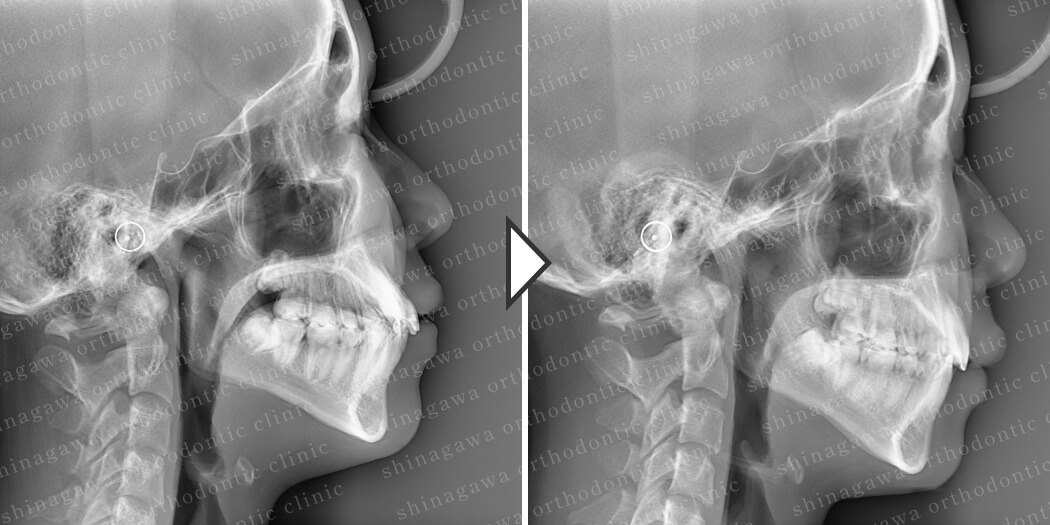

症例5

下顎前突、叢生

| 年齢 | 28 歳 |

|---|---|

| 性別 | 男性 |

| 住所 | 埼玉県浦和市 |

| 主訴 | ガタガタしている, 受け口 |

| 不正咬合の種類(診断) | 叢生, 下顎前突 |

| 装置 | リンガル |

| 抜歯/非抜歯 | UR4, UL4, LR4, LL4 |

| 期間 | 30M |

| 費用 | 1,430,000 円 |

| リスク・副作用 | 矯正治療による歯の移動に伴う痛み, 虫歯, 歯肉退縮, 歯根吸収 |